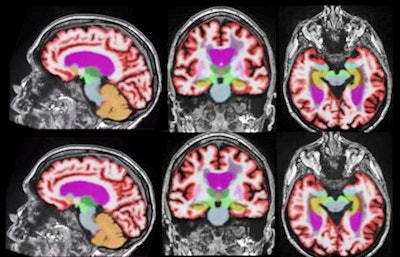

PET imaging showed abnormal radiotracer uptake in the lymph nodes of cancer patients after they received COVID-19 vaccinations. (A) A 57-year-old woman with right upper arm melanoma who received the first dose of the COVID-19 vaccine (Pfizer-BioNTech) in the left deltoid 15 days prior to FDG PET/CT. FDG uptake is observed within left axillary lymph nodes (arrow, SUVmax = 9.3). (B) A 62-year-old man with metastatic prostate carcinoma who received the second dose of COVID-19 vaccine (Pfizer-BioNTech) in the right deltoid seven days prior to C-11 choline PET/CT. Image courtesy of the American Journal of Roentgenology.The second finalist in the Best Radiology Image category comes from a presentation at the European Congress of Radiology in March 2021 by Dr. Suzie Bash, a neuroradiologist at image services provider RadNet. The image series demonstrates how AI can be used to speed up MRI data reconstruction times while maintaining image quality.

AI-based image reconstruction enables significantly faster brain MRI scan times while maintaining quantification accuracy and enhancing image quality. Representative 3D T1-weighted multiplanar images with volumetric segmentation on a 3-tesla scanner. (Left to right): Sagittal, coronal, and axial T1-weighted images with standard protocols (scan time, 5 minutes and 44 seconds) on the top row and deep learning-enhanced accelerated imaging (scan time, 2 minutes and 18 seconds) on bottom row. Images courtesy of Dr. Suzie Bash.

AI-based image reconstruction enables significantly faster brain MRI scan times while maintaining quantification accuracy and enhancing image quality. Representative 3D T1-weighted multiplanar images with volumetric segmentation on a 3-tesla scanner. (Left to right): Sagittal, coronal, and axial T1-weighted images with standard protocols (scan time, 5 minutes and 44 seconds) on the top row and deep learning-enhanced accelerated imaging (scan time, 2 minutes and 18 seconds) on bottom row. Images courtesy of Dr. Suzie Bash.Previous page | 1 | 2 | 3